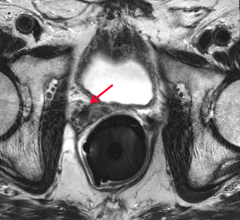

News and new technology innovations concerning how imaging technology can help diagnose and treat prostate cancer can be found on this channel.